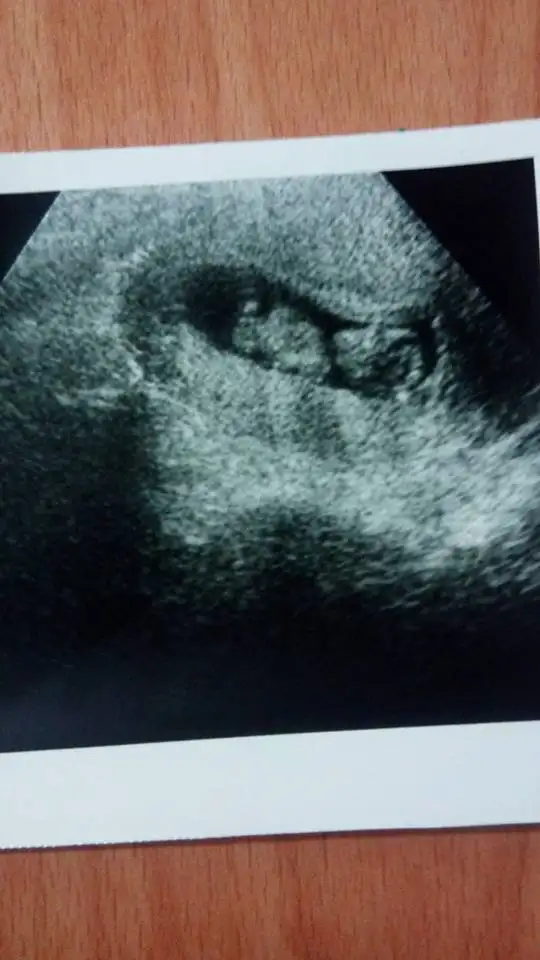

Fotoğrafımız.. Dün aldık 11 hafta 2 günlüktü bugün 3 gün oldu.

Kesin erkek . :KK70: Erkek demeyen kalmadı vallaha. :KK70: Enerjisini yayıyor gelmeden.